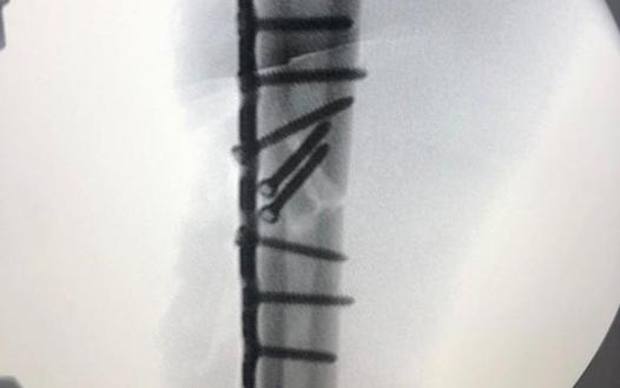

Dodici viti e una placca, giusta la scelta di non scendere in pista per il GP bis a Jerez. Ora la riabilitazione e l'appuntamento di Brno del 9 agosto

Il troppo dolore non gli ha permesso di correre il GP bis di Jerez. Ma la scelta di Marc Marquez è stata sicuramente saggia: le condizioni del suo omero destro sono perfettamente chiare nella foto dell'ecografia che l'otto volte campione del mondo ha caricato su Instagram. Dodici viti e una placca. Non poche. Ora i piani del pilota di Cervera sono quelli di lavorare duramente alla riabilitazione per tornare in azione nel GP di Brno, il terzo appuntamento del Mondiale 2020 fissato fra due domeniche (il 9 agosto).